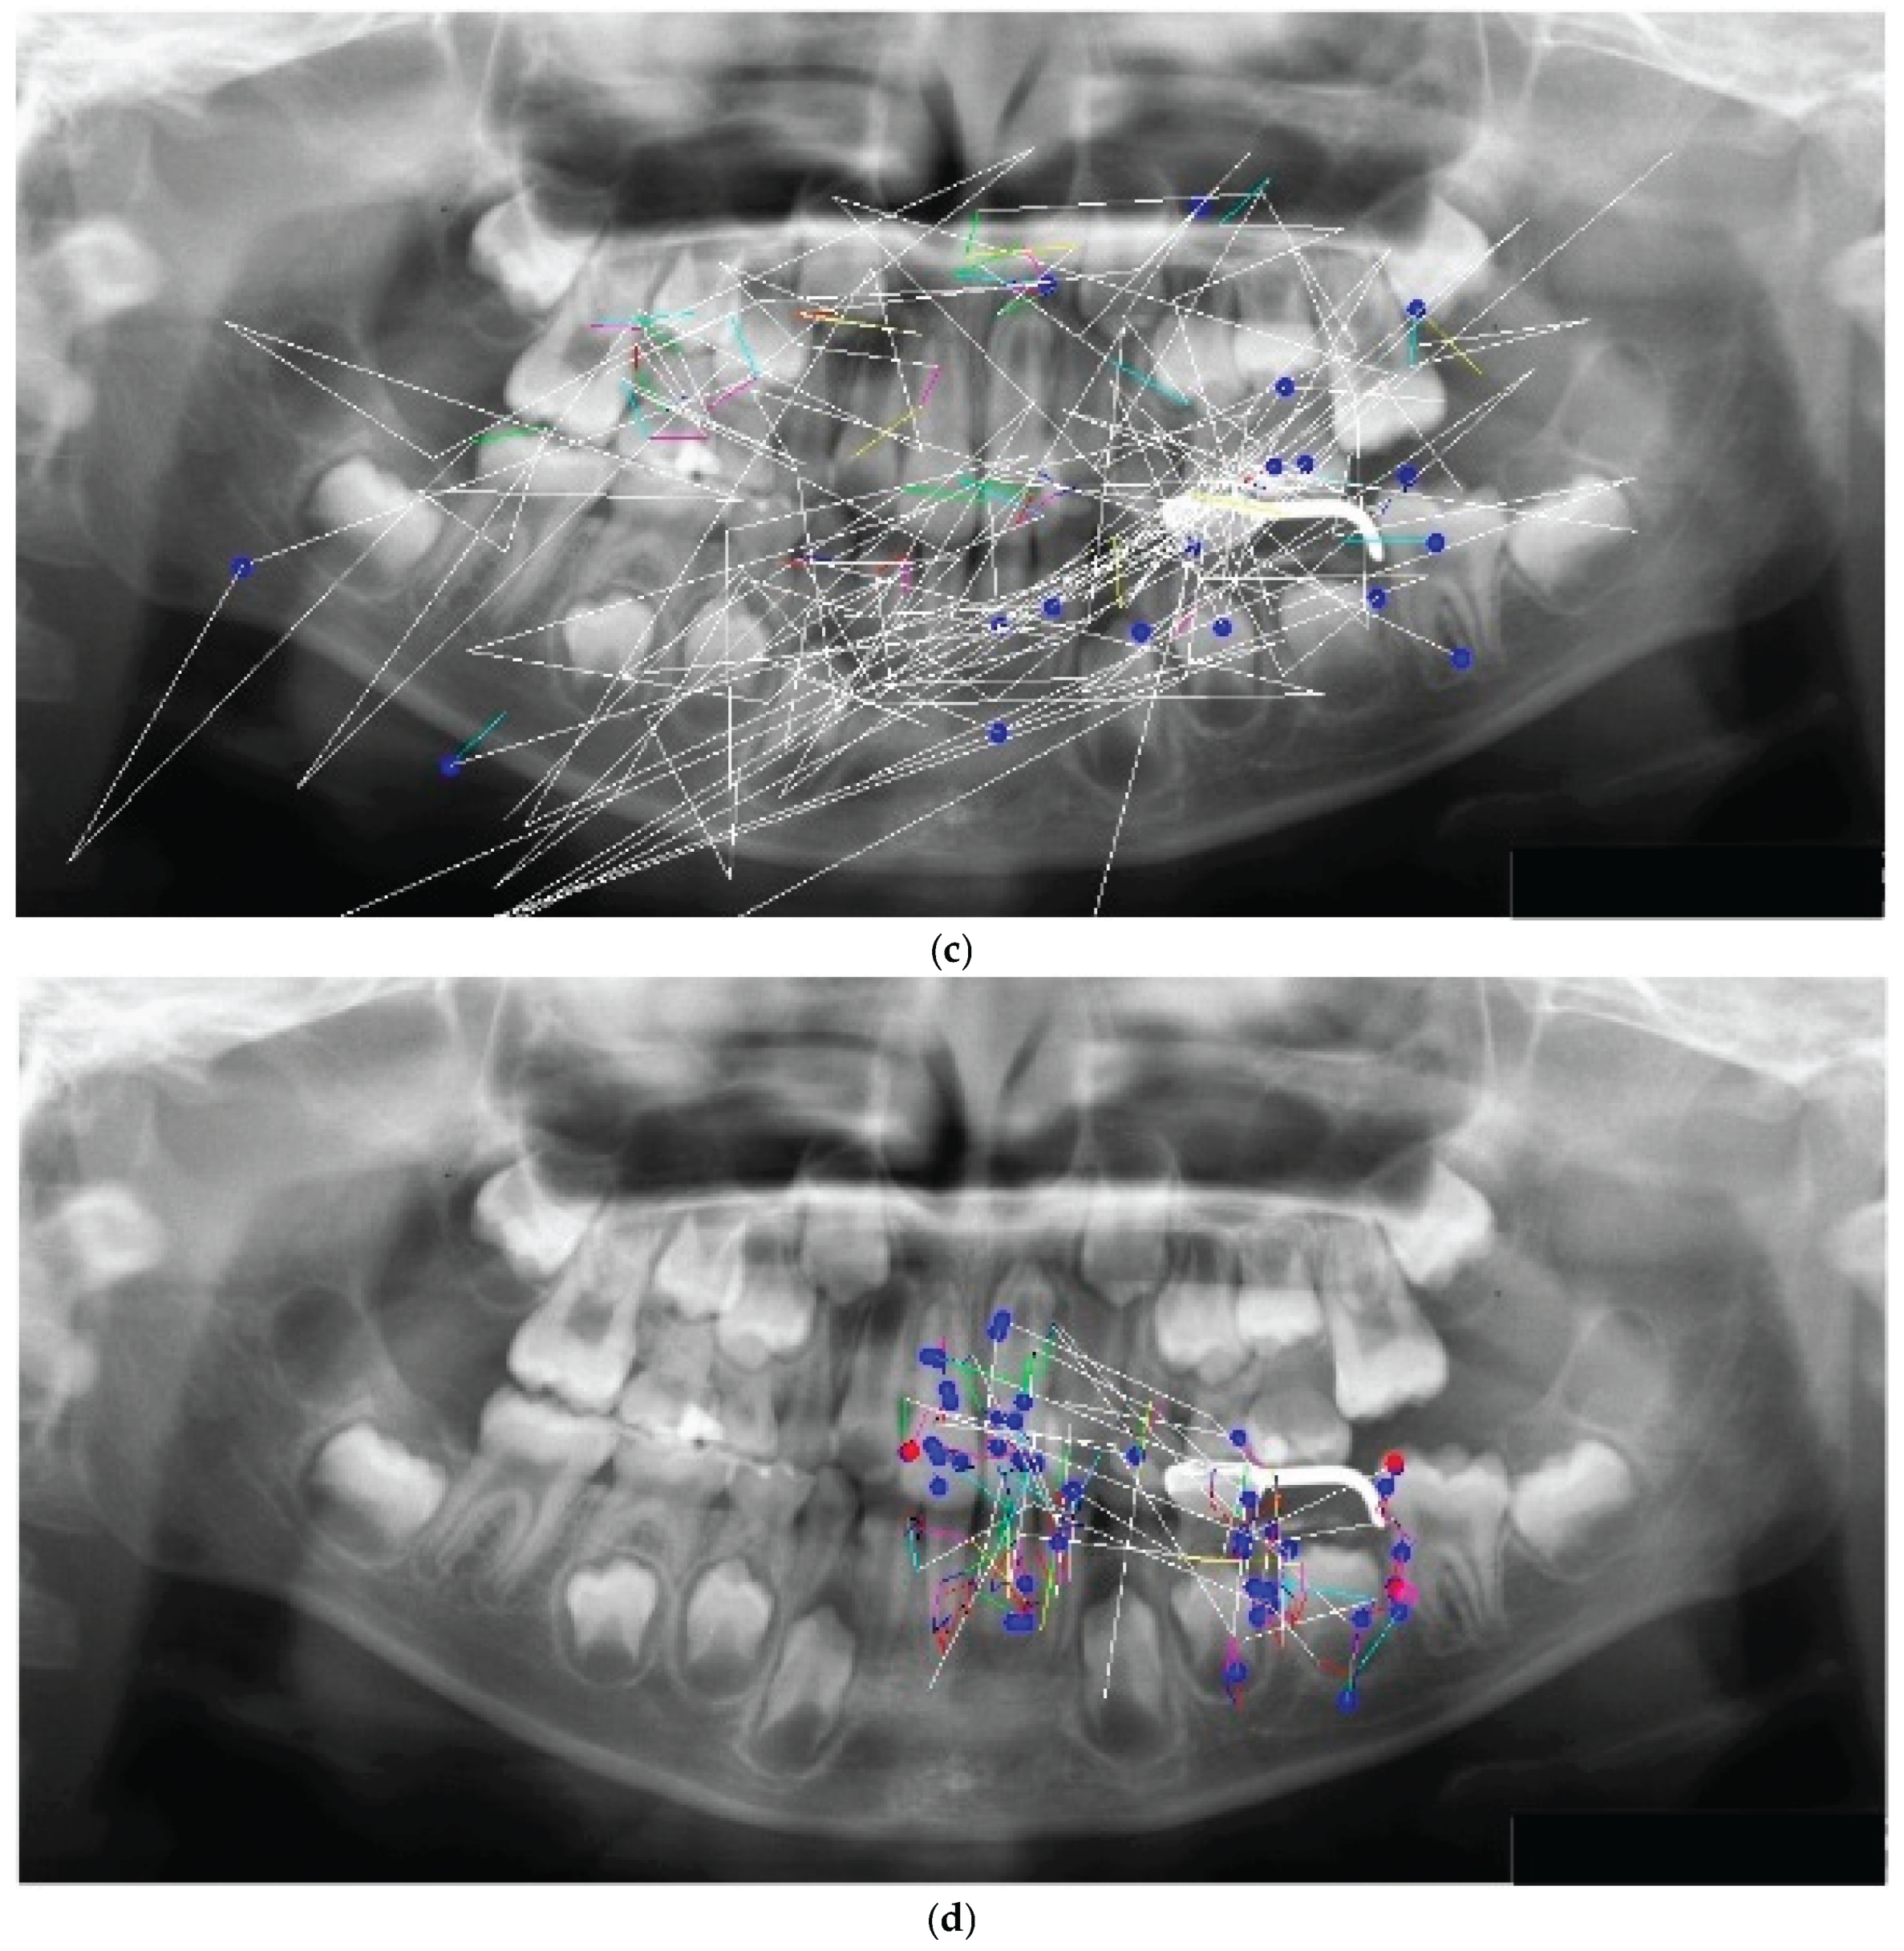

The eye movement patterns were classified into four groups: clockwise (R; n = 16, 29.6%), counterclockwise (L; n = 24, 44.4%), scattered (S; n = 9, 16.7%), and clustered (C; n = 5, 9.3%). No significant sex differences were observed in the distribution of eye movement patterns (χ²(3) = 1.33, p = 0.72). Representative examples of each pattern are shown in Figure 2. High-performing participants in the R group exhibited clockwise scan paths more frequently (Figure 2a), which were characterized by fixations distributed across the entire radiograph and relatively few saccades. An example of the L group is shown in Figure 2b, whereas the S group demonstrated a pattern dominated by saccades with very few fixations (Figure 2c). In the C group, fixation was restricted to specific landmarks (Figure 2d). This indicates a significant association between the categorical variables.

Figure 2. (a) R Group. (b) L Group. (c) S Group. (d) C Group.